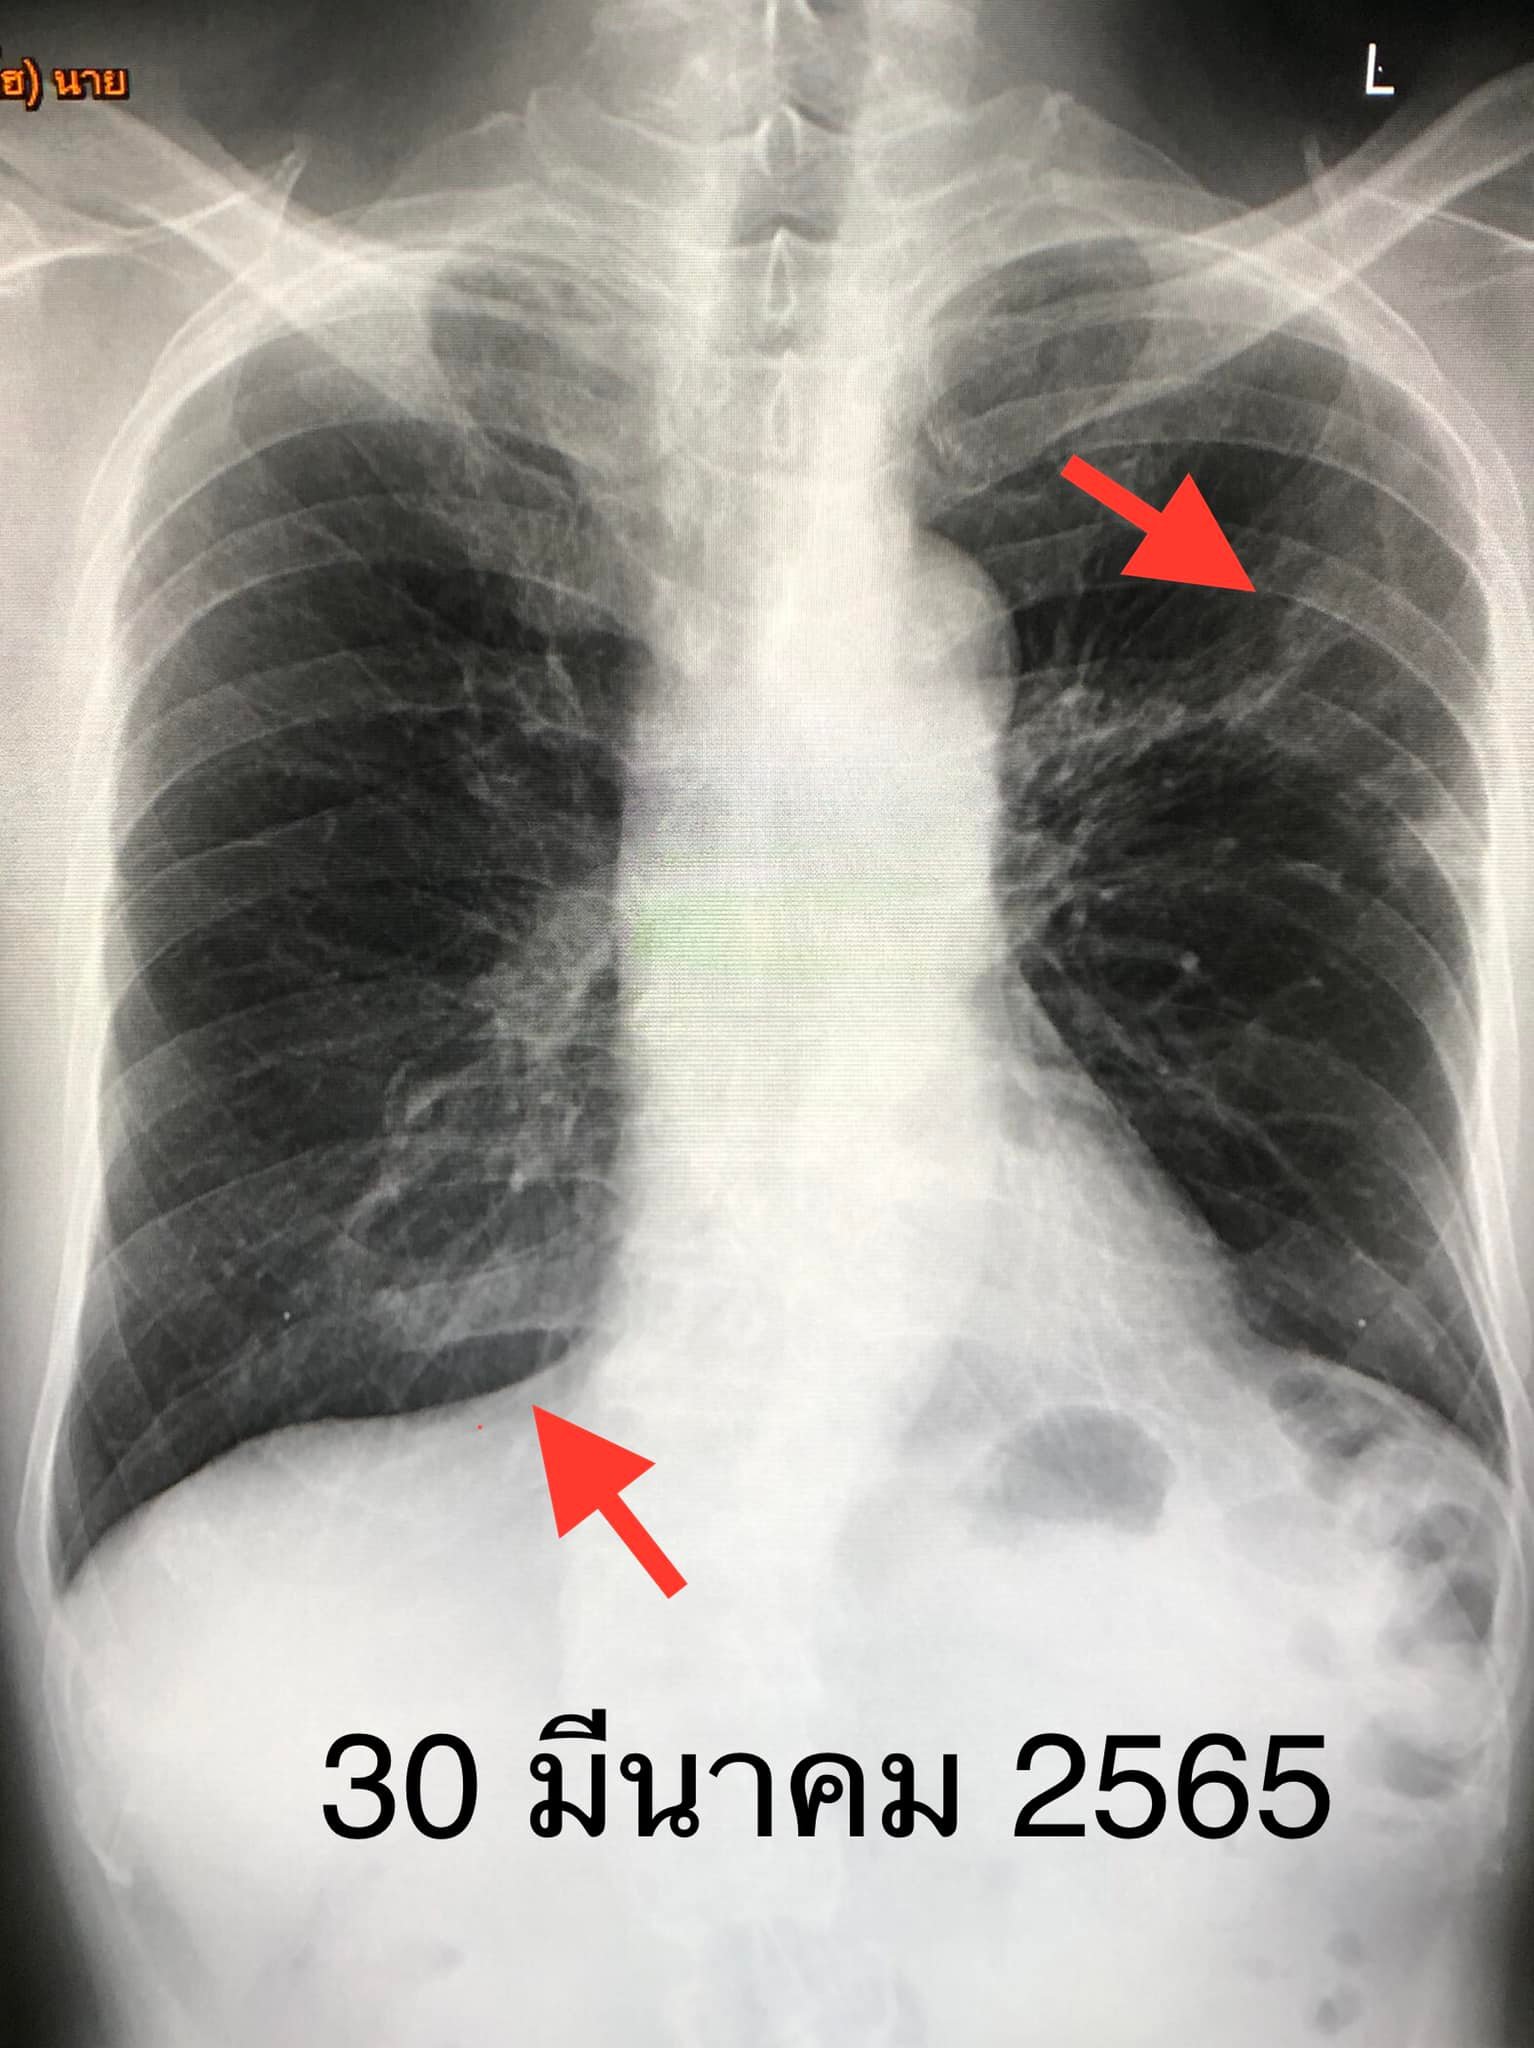

วันที่ 30 มีนาคม 2565 ตรวจร่างกาย ไม่มีไข้ ฟังปอดปกติ วัดระดับออกซิเจนที่ปลายนิ้วปกติ เอกซเรย์ปอดมีฝ้าขาวที่ปอดซ้ายด้านบนและปอดขวาด้านล่าง (ดูรูป) ลักษณะคล้ายวัณโรค ส่งเสมหะตรวจย้อมเชื้อหาวัณโรคให้ผลบวก ยืนยันโดยทำ PCR พบเชื้อวัณโรคไม่ดื้อยาไรแฟมพิซิน ส่งเสมหะเพาะเชื้อวัณโรคและตรวจหาความไวของเชื้อวัณโรคต่อยา

ภาพจาก :นพ.มนูญ ลีเชวงวงศ์